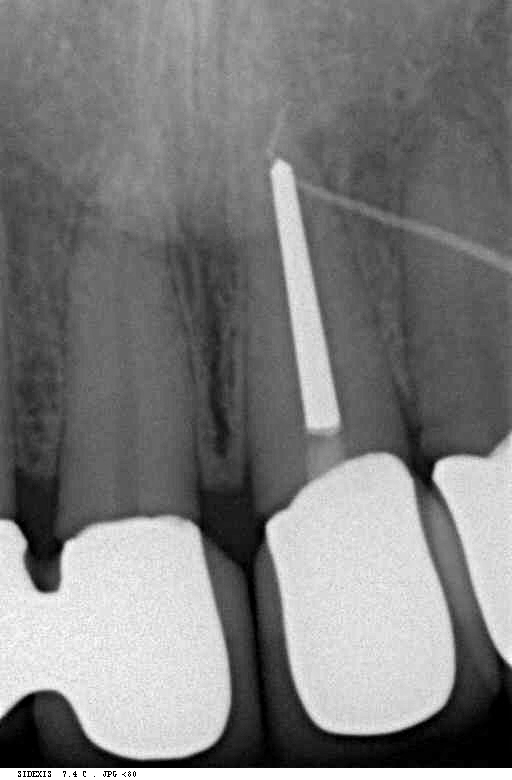

Ausgangsbild Fistel Veröffentlicht 16. März 2012 am 512 × 780 in Erzeugung eines Ferruleeffektes durch Extrusion eines Frontzahnes postendodontisch